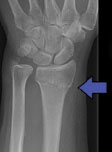

Suggest X-ray

WHAT IS GREENSTICK OR PAEDIATRIC BUCKLE FRACTURES?

Wrist fractures, breaks or greenstick injuries in children are common and can be pretty traumatic. They generally result from sustaining a fall on an outstretched hand, also known as ‘FOOSH’. Common causes of greenstick fracture or paediatric buckle fracture include falling off gym equipment, skateboards and bicycles.. just to name a few. Unlike adult bones, children tend to “bend” before they break and so all of these types iof fractures are stable, they heal quickly and can be treated in a light weight “cast” thaty is water proof and allows children to get on with their lives like swimming!

Signs and symptoms will vary, depending on the severity of the greenstick fracture. Mild fractures might be mistaken for sprains or bruises. More-severe greenstick fractures may cause an obvious deformity, accompanied by significant pain and swelling. Your hand therapist at Action Rehab Hand Therapy Clinic will be able to read your xray, assess your injury and treat it appropriately to maximise function. Greenstick or Buckle Fractures are stable, they do not need surgery and they heal quickly with the right care.

Choosing the right hand therapist starts with them being able to read your X-rays and then fabricate the right brace for you. The therapists at Action Rehab Hand Therapy Clinic are experienced in assessing and reading X-rays.